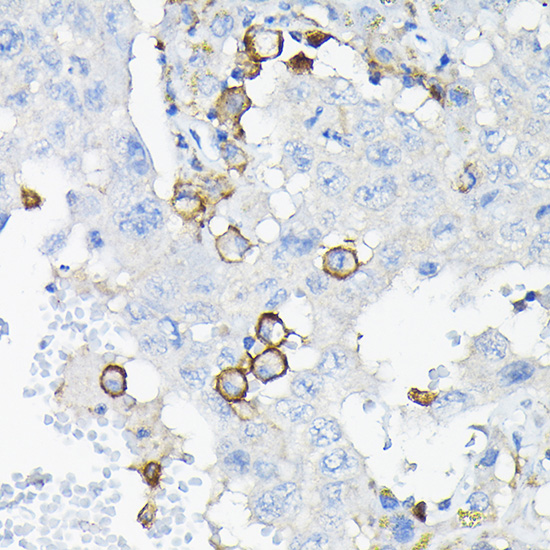

Immunohistochemistry of paraffin-embedded human liver cancer using LILRB4 Rabbit pAb.